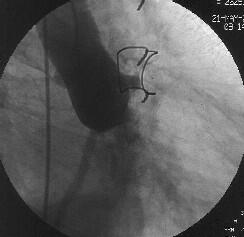

徢椺丗61嵨丄抝惈丅

婛墲楌丗58嵨帪偵DeBakey II宆偺媫惈戝摦柆夝棧偵偰Bentall弍(Piehler朄)傪巤

峴丅59嵨帪偵偼暊晹偵媫惈戝摦柆夝棧傪敪徢偟丄堦帪峈嬅屌椕朄傪拞抐偟偨偑偦

偺屻嵞奐丅

尰昦楌丗暯惉14擭5寧屵慜0帪傛傝摢栩晹捝偑弌尰偟丄嫻晹傊捝傒偑曻嶶偡傞傛偆

偵側傝7帪偵摉堾傪媬媫庴恌偝傟傑偟偨丅

棃堾帪尰徢丗寣埑86/66mmHg丆柆攺106/min丒惍丅岥怬偵僠傾僲乕僛傪擣傔偨丅怱

揹恾偱QRS暆偺奼戝偲I, aVL, V4-6偵ST忋徃傪擣傔丄媫惈怱嬝峓嵡偵傛傞怱尨惈

僔儑僢僋偲恌抐偟丄嬞媫僇僥乕僥儖専嵏傪巤峴偟傑偟偨丅

怱憻僇僥乕僥儖専嵏丗RCA偵嫹嶓昦曄傪擣傔傑偣傫偱偟偨偑丄LCx傊collateral傪

擣傔傑偟偨乮Figure1乯丅堷偒懕偄偰LCA偺憿塭傪帋傒傑偟偨偑丄JL僇僥乕僥儖偑

偳偆偟偰傕engage偱偒傑偣傫偱偟偨丅戝摦柆憿塭傪巤峴偟丄塃姤愲偺塃懁忋曽偵

憿塭嵻偺pooling傪擣傔傑偟偨乮Figure2乯丅擖岥晹偱姰慡暵嵡偟偰偄傞偲峫偊摨

晹埵偵懳偡傞僀儞僞乕儀儞僔儑儞傪巤峴偡傞偙偲偲偟傑偟偨丅擖岥晹偑塃懁忋曽

偵懚嵼偡傞偨傔丄僈僀僨傿儞僌僇僥乕僥儖偼丄JR僇僥乕僥儖傪巊梡偟傑偟偨

乮Figure3乯丅

側偍丄恖岺寣娗偺擖岥晹偺摨掕偵旕忢偵擄廰偟丄専嵏奐巒屻偡偱偵栺30暘偑宱夁

偟偰偄傑偟偨丅屇媧忬懺偑偝傜偵埆壔偟偮偯偗偨偨傔丄恖岺屇媧娗棟偲偟傑偟

偨丅寣埑傕掅壓偟偰偄傑偟偨偑丄DOA5兞掱搙偱80-90戜傪堐帩偟偰偄傞忬嫷偱偟

偨丅IABP偺憰拝傕峫偊傑偟偨偑丄戝摦柆夝棧偑懚嵼偟偰偄傞偨傔巊梡偟傑偣傫偱

偟偨丅

姤摦柆僀儞僞乕儀儞僔儑儞丗僈僀僨傿儞僌僇僥乕僥儖偺engage偑埆偄偨傔丄儔僕

僆僼僅乕僇僗丒儚僀儎乕偱僇僥乕僥儖傪屌掕偝偣側偑傜彊乆偵儚僀儎乕傪恑傔偰

偄偔偲丄彮偟偯偮寣娗偑憿塭偝傟傞傛偆偵側傝丄恖岺寣娗偲LMT偺暙崌晹偵崅搙

嫹嶓傪擣傔傑偟偨乮Figure4乯丅傑偨丄嵍姤摦柆撪偵嫄戝側寣愷傪擣傔傑偟偨丅

摉帪寣愷媧堷偺僨僶僀僗偑側偔丄媧堷偼偱偒傑偣傫偱偟偨丅暙崌晹偵懳偟偰丄

MAVERICK4.0mm偱POBA傪峴偄丄偦偺屻LAD偵嫄戝側寣愷偑棳傟偰偄偔偺偑妋擣偝傟

傑偟偨乮Figure5乯丅NIR4mm僗僥儞僩傪棷抲偟暙崌晹嫹嶓偼夵慞偟傑偟偨偑丄LAD

偺no flow傪擣傔傑偟偨丅nicorandil偍傛傃UK傪姤拲偟偨偲偙傠丄flow偑夵慞偟

偨偨傔庤媄傪廔椆偟傑偟偨乮Figure6乯丅